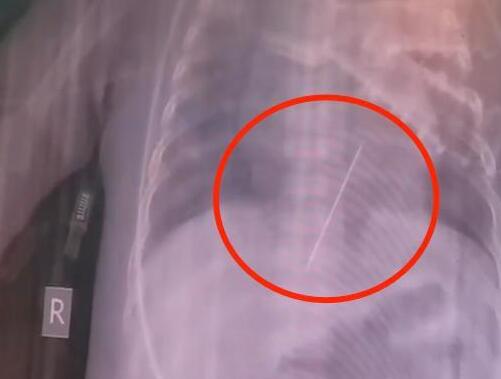

6月16日中午,記者從合肥市第二人民醫(yī)院了解到,孩子送來時,臍帶還沒有扎好,目前孩子還在暖箱里,檢查正在按流程開展。